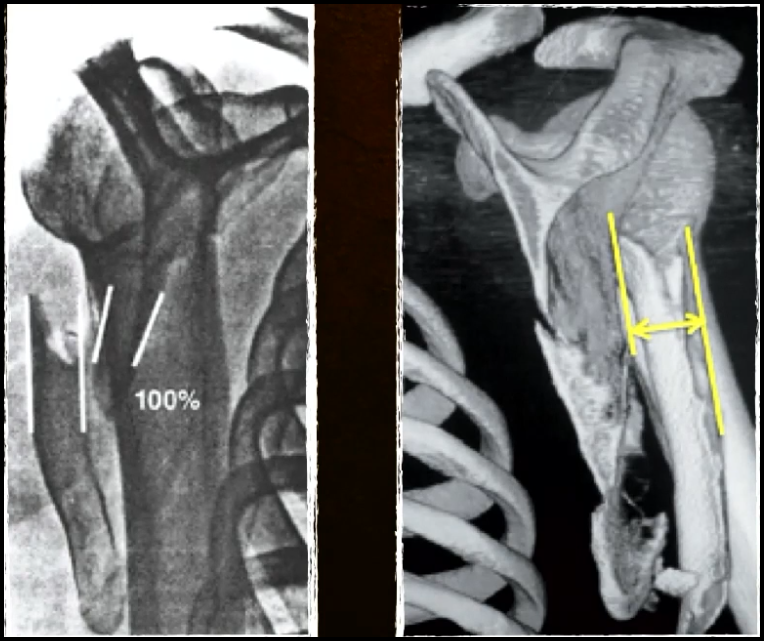

Avaliação deslocamento mediolateral ?

Aceitável até 20 mm

Avaliação translação ?

Aceitável se < 100%